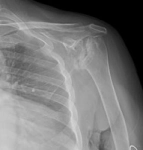

Şikayet:Sol omuzda hareket kısıtlılığı.

Özgeçmiş:10 yıl önce yaygın eklem ağrıları olan hasta RA tanısı almış KS ve MTX kullanım öyküsü mevcut hasta kortikosteroid ile takipli.

Muayene:Sol omuz: Flex: 0-70°, Abd: 0-70°, İstirahatte VAS: 0, Hareket ile VAS:1-2, GYA’de bağımsız. Sistemik tutulum ve organ tutulumu yok. Diğer fizik muayene doğal ellerde deformite yok.

Sol Omuz MRG: Glenoidde kortikal düzensizlikler, lokalize defektif alanlar ve bu düzeyde subkondral milimetrik kistlerin eşlik ettiği medüller hafif hiperintens ödem izlenmektedir. Humerus baş kesiminde medialde de geniş bir alanda defektif görünüm mevcuttur. Buna komşu humerus başında milimetrik kistler ve medüller ödem izlenmektedir.

Humerus başında ve glenoid de osteofitik dejeneratif değişiklikler mevcuttur. Gleno-humeral eklem aralığı anterior inferiorda daralmıştır.Eklem aralığında sıvı miktarında belirgin artış izlenmedi.

Humerusta tüberkülüm majusta milimetrik kist - medüller ödem benzeri sinyal değişikliği dikkati çekmektedir.

Akromioklaviküler eklemde minimal dejeneratif hipertrofi izlenmekte olup eklem aralığı yaklaşık 5 mm ölçülmüştür ve normal sınırlar içerisindedir. Subakromial yağ mesafesi basılıdır. Akromion Tip 2 konfigürasyondadır. Glenoid labrumlar değerlendirilemedi. Biceps uzun başı tendonu normaldir. Supraspinatus tendonunda tendinozis izlenmektedir.

Resim 2

Ön tanıda romatoid artrite bağlı eklem tutulumu, avasküler nekroz, Charcot eklemi (periferik nöropati- servikal radikülopati?) olasılıkları tartışıldı. Hastanın ileri derecedeki eklem kısıtlılığı ve buna bağlı gelişen omuz çevresi kaslarda atrofisi olması sebebi ile artroplastiden fayda görebileceği öngörüldü.